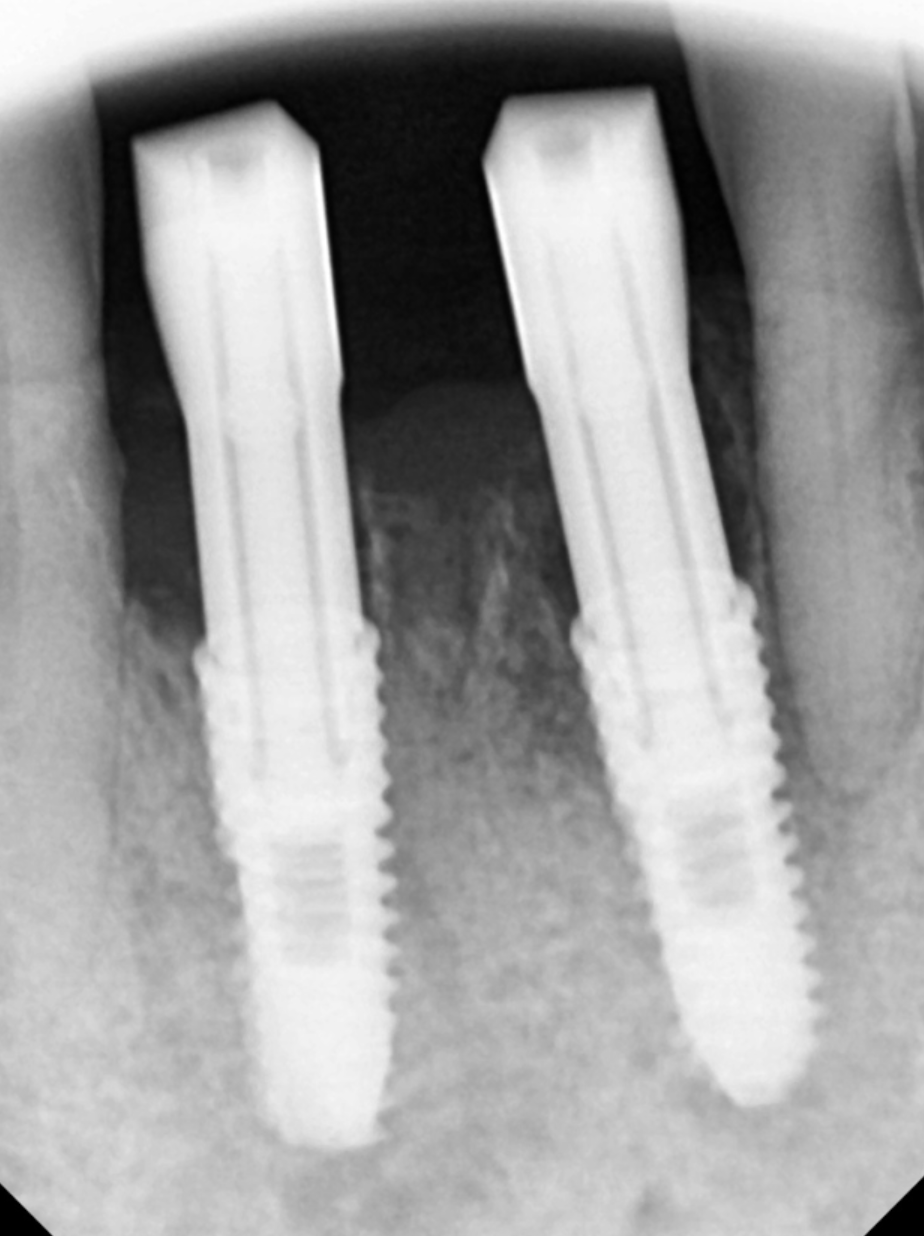

240622

아래 앞니는 잇몸뼈가 약해서... 더 위험합니다

하악 전치부

그러니까 아래 앞니는 잇몸뼈가 얇아

작은 염증에도 뼈 소실이 빠르게 진행됩니다.

이런 해부학적인 특징 때문에 임플란트 역시

고난이도가 요구됩니다.